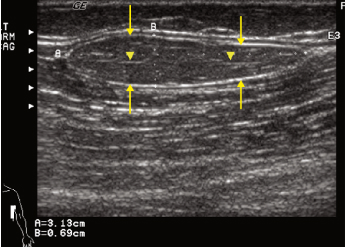

Ultrazvučni pregled mekih tkiva

Ultrazvučna eksploracija mekih tkiva linearnom sondom omogućava pregled mekih tkiva vrata, pazušne jame i u preponama, sa opisom dimenzija i morfologije štitaste žlezde, sa kolornom mapom. Utvrđuje se i morfologija paraštitastih i pljuvačnih žlezda , kao i limfnih žlezdi u podvilićnom regionu , jugularno, iznad ključnjače i potiljačno. U pazušnoj jami i preponama identifikuje se prisustvo i veličina limfnih žlezdi. Usled visoke reyolutivne sposobnosti linearne sonde moguća je i eksploraija kožnih promena (lipomi/ateromi)